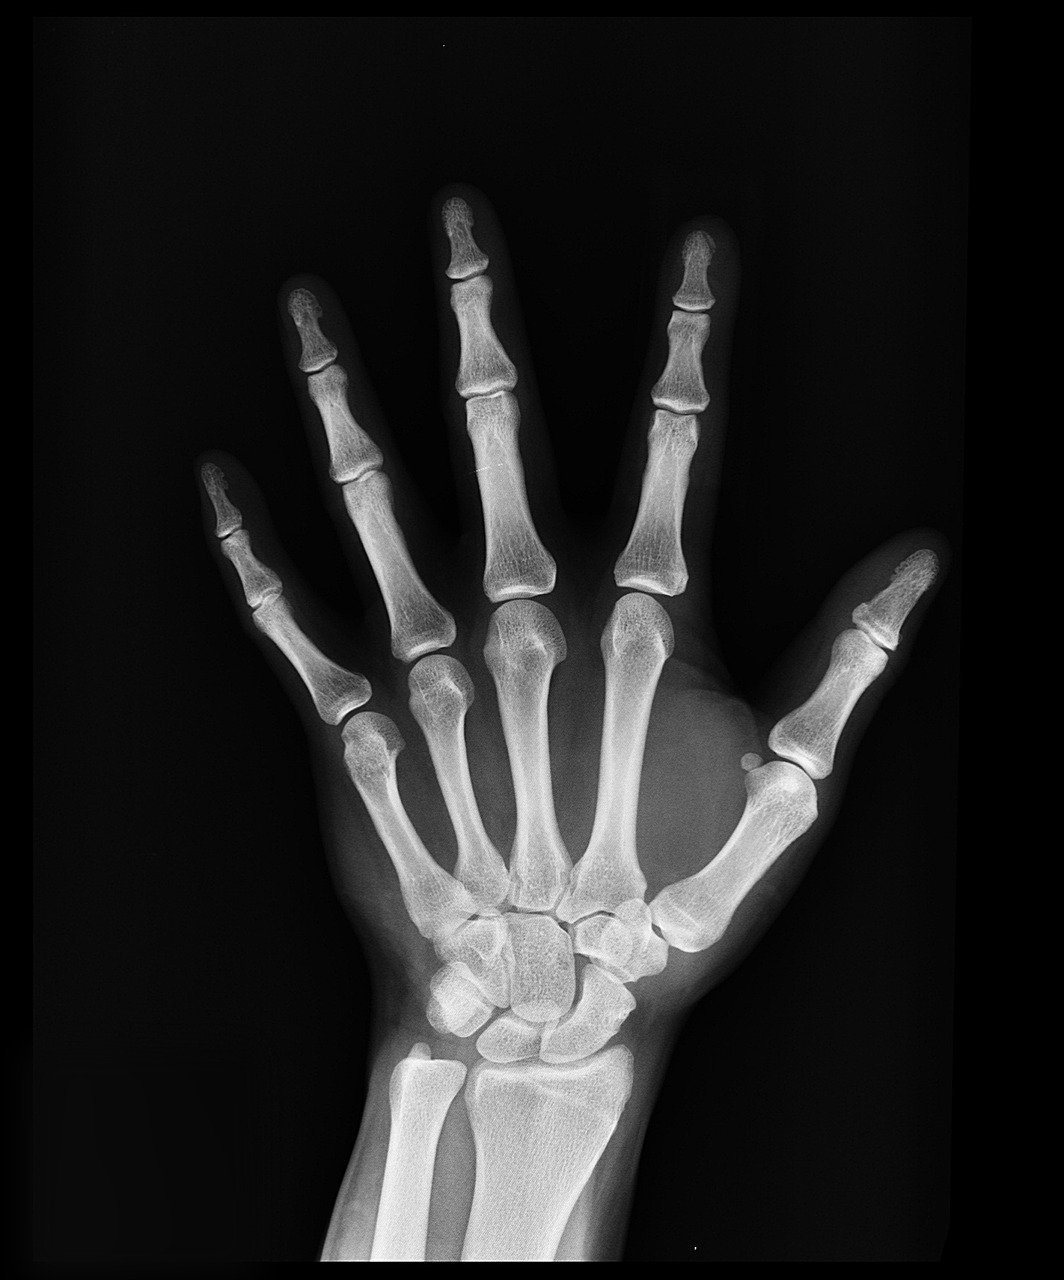

3. X-rays by Wilhelm Röntgen (1895)

Wilhelm Röntgen stumbled on X-rays while experimenting with cathode rays in 1895. A glowing screen across the room revealed invisible rays passing through objects. He captured the first image of his wife’s hand, bones stark against flesh.

Doctors now peer inside bodies without surgery. Broken bones, tumors, and dental issues get diagnosed swiftly. This tool speeds treatment and saves lives in emergencies every day.[3]